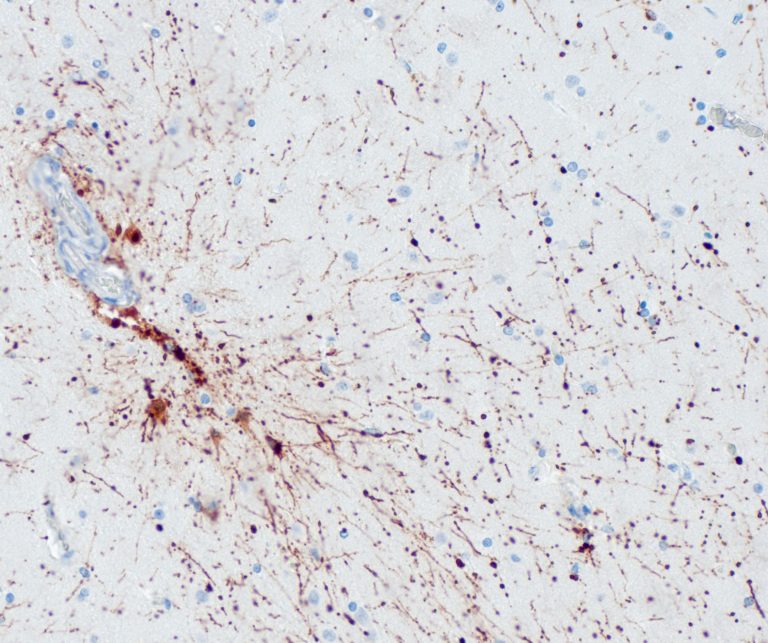

Neuropathology